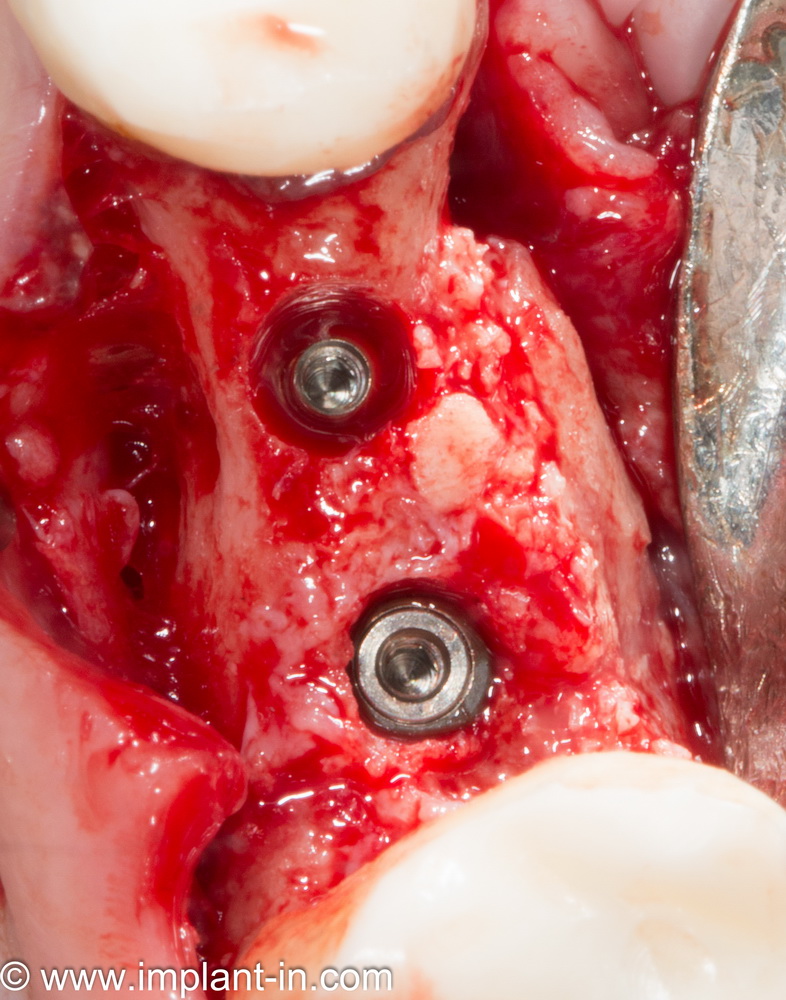

Остеопластические операции: факторы успеха